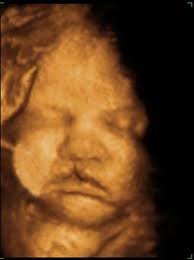

Chromosomal anomalies mortality. Surprisingly 3d surface rendering revealed a cleft lip on the right side figure 2. The anatomy scan is a level 2 ultrasound which is typically performed on pregnant women between 18 and 22 weeks. I have 2 other pictures one head on and another profile pic that i will upload if i can figure out how to attach more photos.

Midline sagittal views normal. Ultrasound pic looks like cleft lip and im freaking out. Ultrasound of cleft lip and palate. What does cleft lip look like in ultrasound i think you can see it easily especially the 3d 4d one.